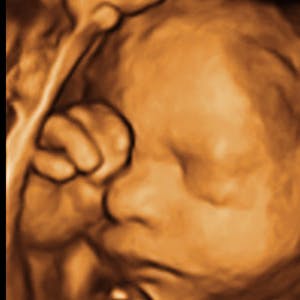

Gravid

Vi gør en dyd ud af at klæde dig godt på både før, under og efter din graviditet. Vi ved, at der kan komme mange spørgsmål til din graviditet, fødsel, amning, din babys udvikling og mange flere emner, derfor har vi samlet guides, tips & tricks samt læsernes egne fortællinger i dette gravid univers.